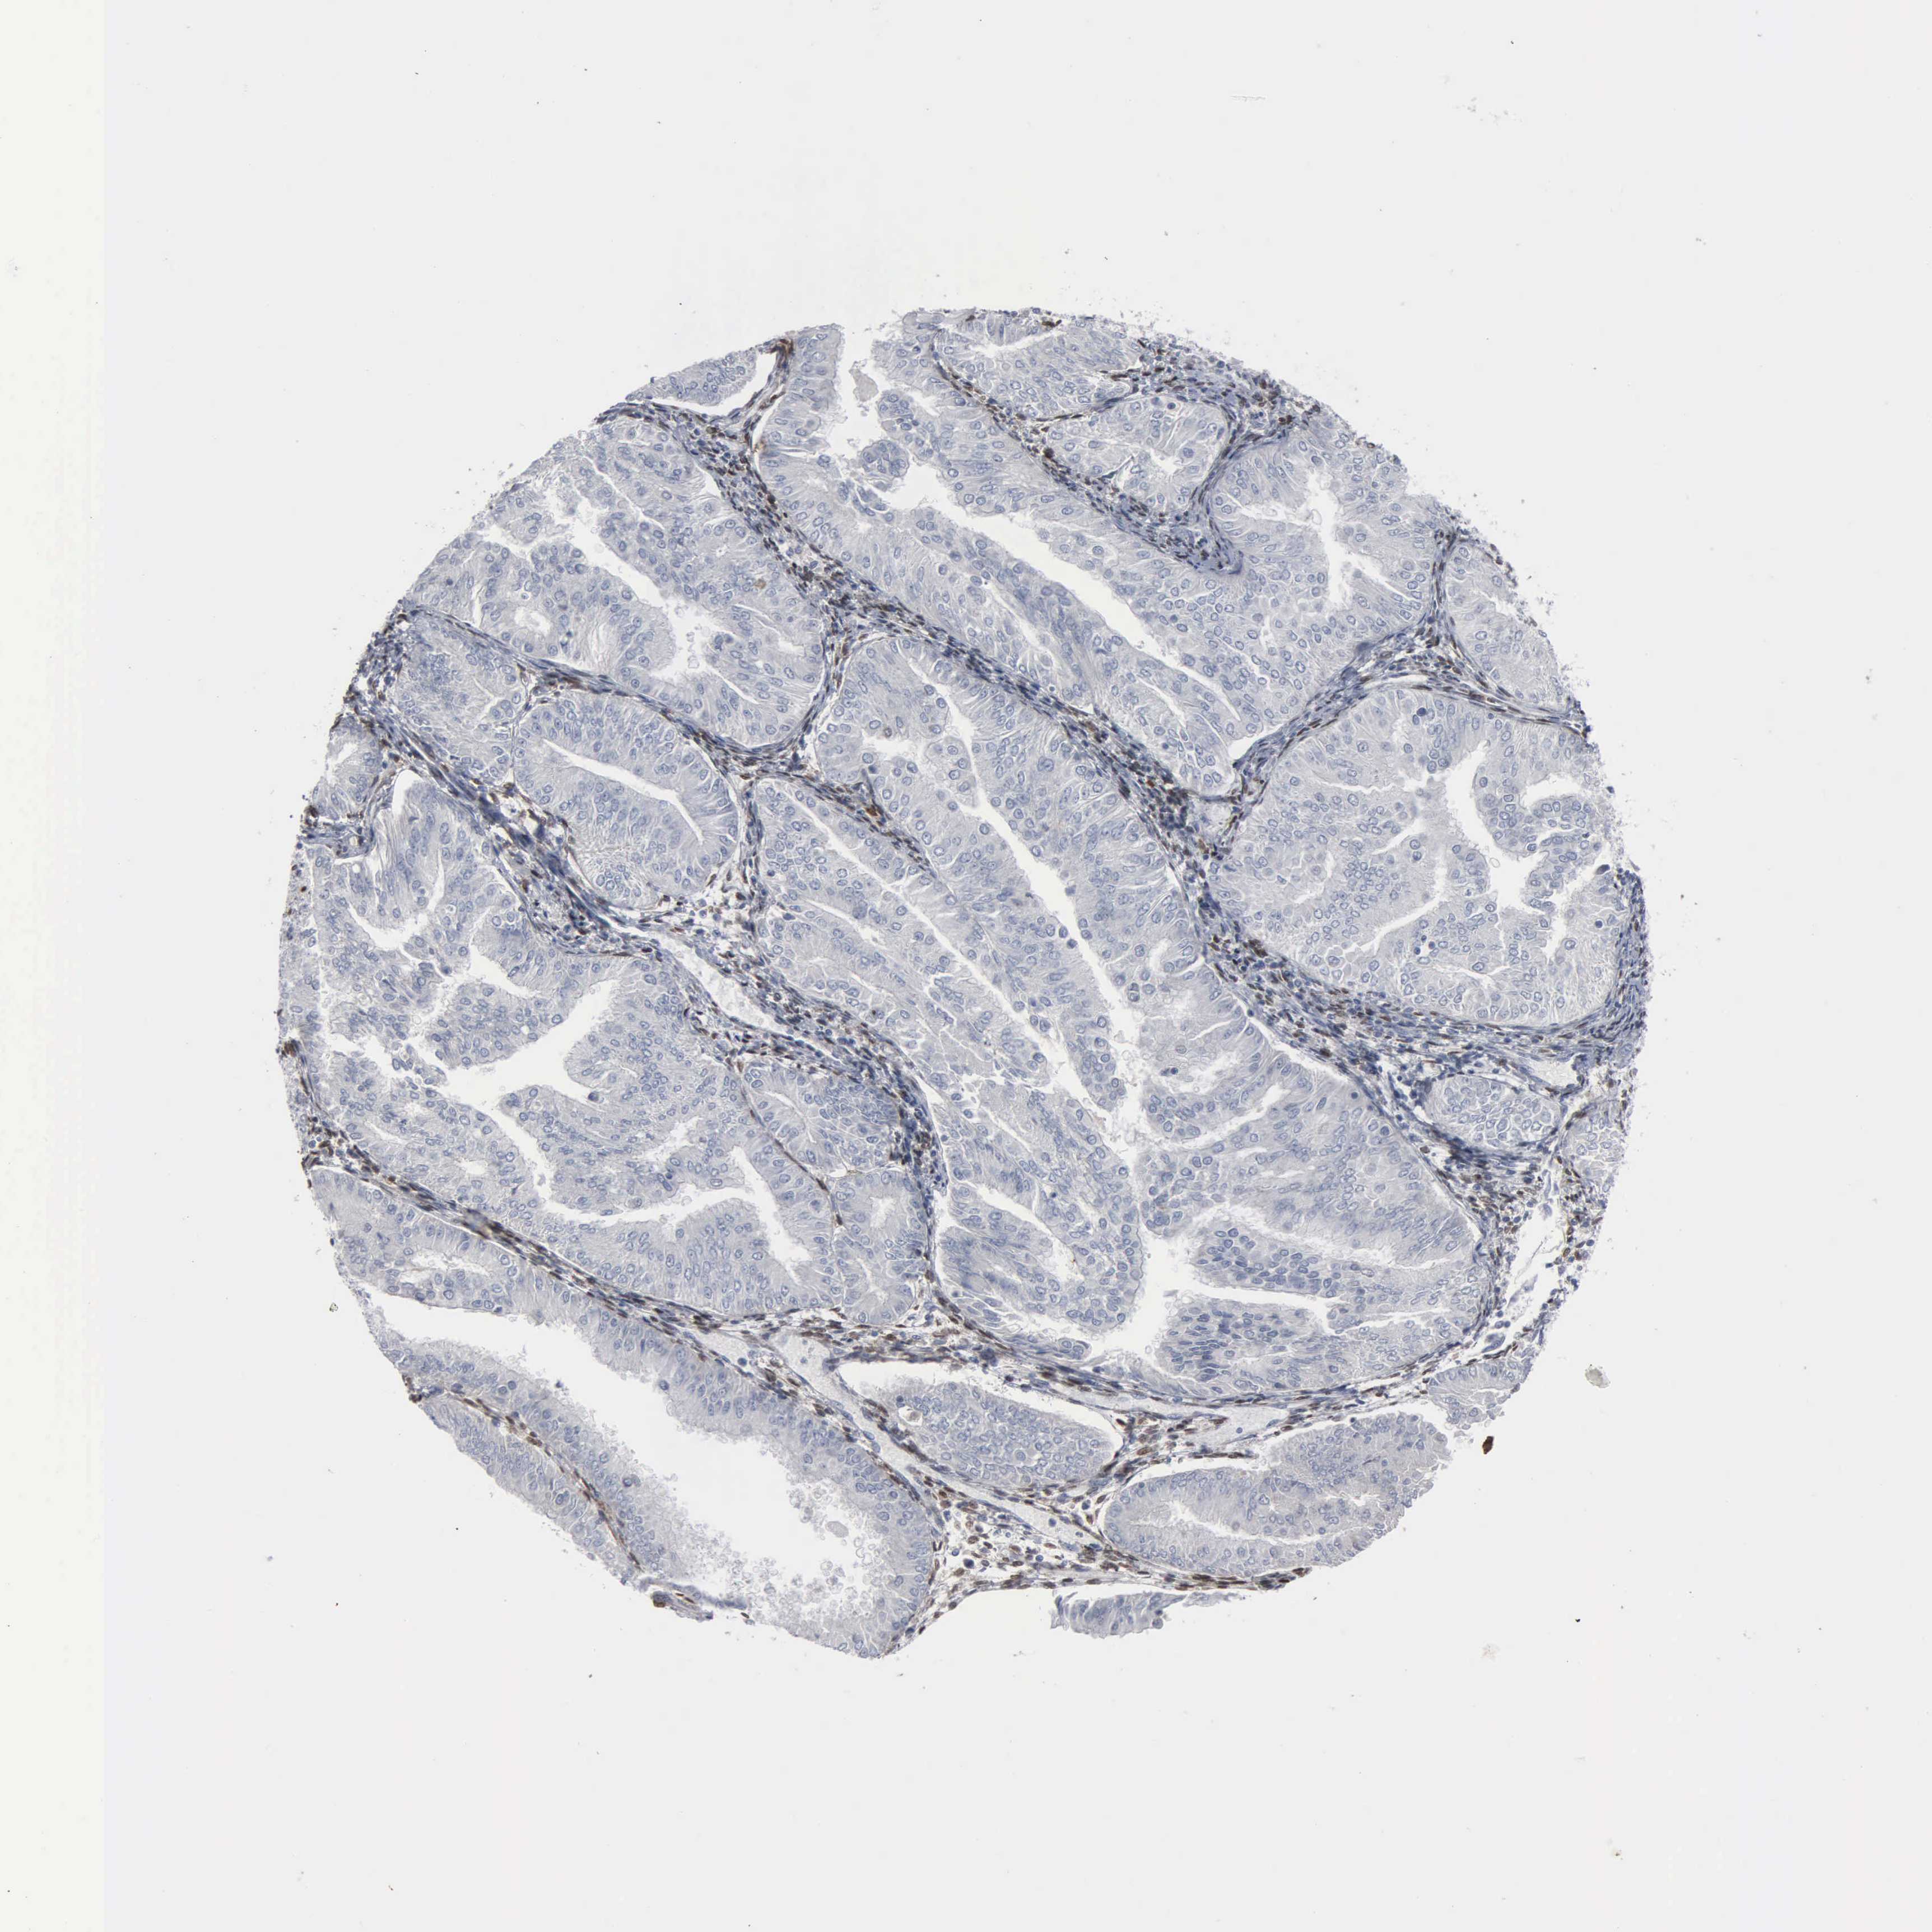

ENDOMETRIAL CANCER - Protein expressioni

A mouse-over function shows sample information and annotation data. Click on an image to view it in a full screen mode. Samples can be filtered based on level of antibody staining by selecting one or several of the following categories: high, medium, low and not detected. The assay and annotation is described here.

Note that samples used for immunohistochemistry by the Human Protein Atlas do not correspond to samples in the TCGA dataset.

Antibody stainingi

Antibody staining in the annotated cell types in the current human tissue is reported as not detected, low, medium, or high, based on conventional immunohistochemistry profiling in selected tissues. This score is based on the combination of the staining intensity and fraction of stained cells.

Each image is clickable and will lead to virtual microscopy that enables deeper exploration of all samples and also displays staining intensity scores, fraction scores and subcellular localization as well as patient and tissue information for each sample.

Antibody HPA065502

Antibody CAB000125

Staining

High

Medium

Low

Not detected

Intensity

Strong

Moderate

Weak

Negative

Quantity

>75%

75%-25%

<25%

None

Location

Nuclear

Cytoplasmic/membranous

Cytoplasmic/membranous,nuclear